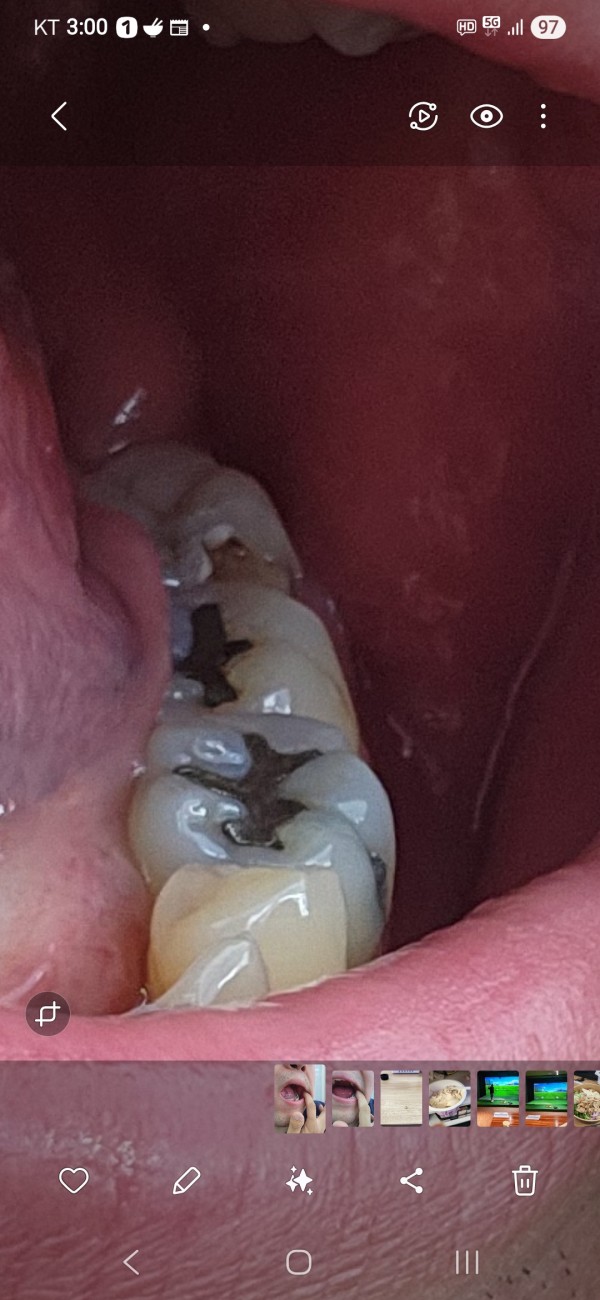

왼쪽 아래 어금니쪽 아말감 치료했던 치아가 오늘 흔들거리더니 바깥쪽이 떨어져 나왔는데 통증도없고 만지거나 이쪽으로 뭔가 먹을때도 통증은없던데 이런경우 어떤치료하고 비용은 얼마정도 들까요..? 가게영업중이라 한번에 알아보고 가려고 질문드립니다..

답변이 늦어 미안합니다. 부서진 치아는 하악 왼편 사랑니로 보입니다. 보통 관리되지 않는 사랑니는 지금처럼 파절시 발치를 추천합니다. 사랑니가 아닌 치아라면 충치범위에 따라 신경치료를 하고 크라운(덮어씌우기)을 하게 되는데 재료에 따라 30~55만 정도비용이 듭니다.  현재 치아가 사랑니지만 살려쓰고 싶으시면 기존치아처럼 신경치료 후 크라운을 하시고 아니라면 발치를 추천드립니다.